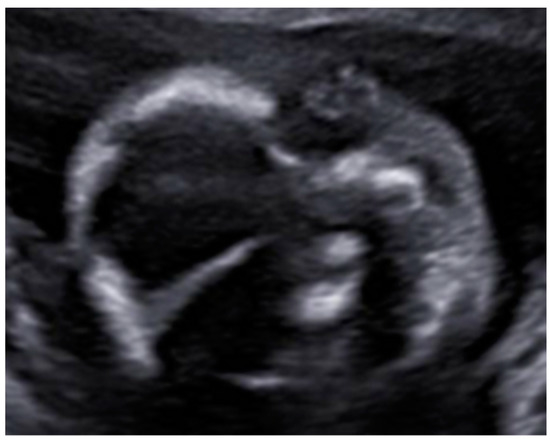

3. Results: Case Presentation